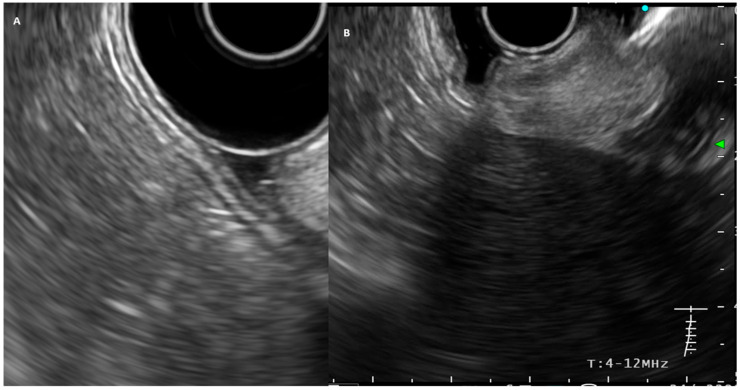

胃癌仍然是全球癌症相关死亡的第四大原因。晚期疾病与不良预后相关,强调通过内窥镜早期诊断的重要性。除了预后外,疾病程度对指导治疗策略也起着关键作用。因此,准确的局部分期(T和N分期)对于最佳预后和治疗计划至关重要。内镜超声(EUS)长期以来一直是这方面的重要工具,计算机断层扫描(CT)和最近的正电子发射断层扫描-计算机断层扫描(PET-CT)作为替代成像方式。早期胃癌定义为肿瘤侵袭局限于粘膜或粘膜下层,EUS在早期胃癌的评估中特别有价值。这些肿瘤越来越多地通过内镜切除技术进行治疗,改善了治疗后的生活质量。最近,EUS也被用于新辅助化疗后的再分期过程,帮助评估肿瘤的可切除性和预后。它的性能可以通过应用新兴技术,如对比增强超声、EUS弹性成像和人工智能系统进一步提高。在晚期不可切除的疾病中,胃出口梗阻(GOO)等并发症严重影响患者的生活质量。在这种情况下,eus引导下的胃肠造口术(EUS-GE)为外科胃空肠造口术提供了一种侵入性较小的选择。这篇综述总结并批判性地分析了EUS在胃癌中的作用,强调了其在不同疾病阶段的应用,并评估了其相对于其他诊断方式的表现。

Gastric cancer remains the fourth leading cause of cancer-related mortality worldwide. Advanced disease is associated with a poor prognosis, emphasizing the critical importance of early diagnosis through endoscopy. In addition to prognosis, disease extent also plays a pivotal role in guiding management strategies. Therefore, accurate locoregional staging (T and N staging) is vital for optimal prognostic and therapeutic planning. Endoscopic ultrasound (EUS) has long been an essential tool in this regard, with computed tomography (CT) and, more recently, positron emission tomography-computed tomography (PET-CT) serving as alternative imaging modalities. EUS is particularly valuable in the assessment of early gastric cancer, defined as tumor invasion confined to the mucosa or submucosa. These tumors are increasingly managed by endoscopic resection techniques offering improved post-treatment quality of life. EUS has also recently been utilized in the restaging process after neoadjuvant chemotherapy, aiding in the evaluation of tumor resectability and prognosis. Its performance may be further enhanced through the application of emerging techniques such as contrast-enhanced endosonography, EUS elastography, and artificial intelligence systems. In advanced, unresectable disease, complications such as gastric outlet obstruction (GOO) severely impact patient quality of life. In this setting, EUS-guided gastroenterostomy (EUS-GE) offers a less invasive alternative to surgical gastrojejunostomy. This review summarizes and critically analyzes the role of EUS in the context of gastric cancer, highlighting its applications across different stages of the disease and evaluating its performance relative to other diagnostic modalities.